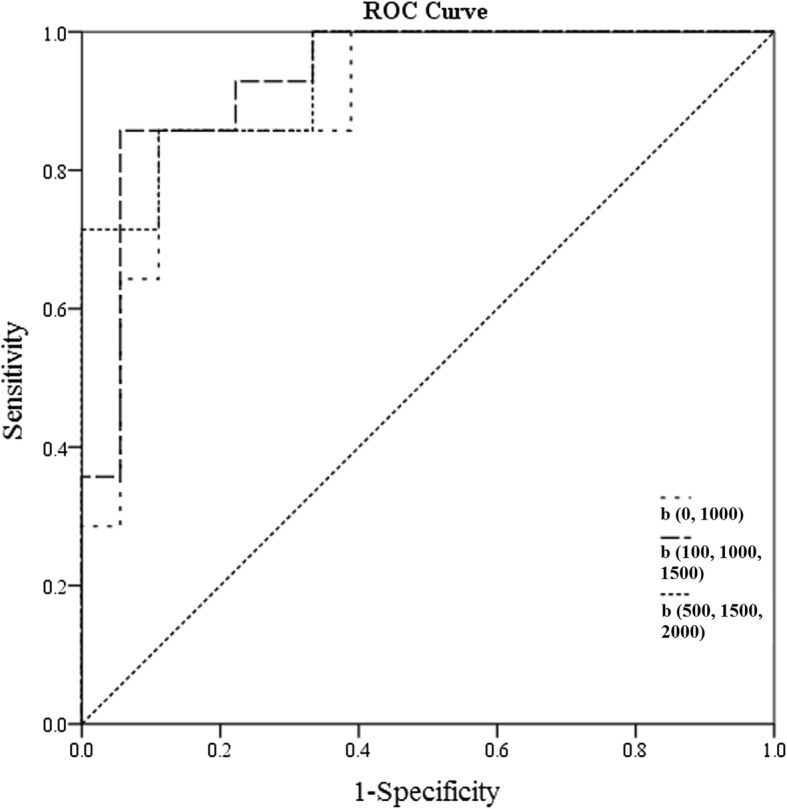

There was a significant negative correlation between the mean ADC values and T stages for patients with rectal cancer in all b-value combinations. The Spearman correlation coefficients for those combinations ranged from − 0.759 to − 0.407. The results of the ROC analysis are shown in Table 2 and Additional file 1: Table S1. Overall, the AUC values ranged between 0.714 and 0.938 for evaluating the mean ADC values and T stages. Representative examples of the images in rectal cancer patients with T1, T2 and T3 stages are shown in Figs. 3, 4, 5, respectively. Figure 6 shows the ROC curves of the mean ADC for discriminating rectal cancer between T1–2 and T3 stages for the representative b-value combinations.

Fig. 6.

Receiver operating characteristic (ROC) curves of the mean ADC for discriminating rectal cancer between T stages 1 + 2 and 3 for the representative b-value combinations. Areas under receiver operating characteristic curves are 0.901 (0.743–0.978), 0.937(0.791–0.992), and 0.933(0.785–0.991) for b(0, 100), b(100, 1000, 1500), and b(500, 1500, 2000) combinations, respectively

Optimized b-value distribution

To obtain the optimized b-value distribution, α was defined and calculated according to the above-mentioned formula, in which ICC, CV, bias, AUC and ρ values were taken into consideration. The results of the α values are also presented in Table 2. b-value combinations with the top three α values are b(0, 1000 s/mm2), b(500, 1500, 2000 s/mm2) and b(100, 1000, 1500 s/mm2) for α = 2.581, 2.571 and 2.569, respectively. Therefore, the optimal b-value combination is b-value = 0 and 1000 s/mm2, which has the highest α = 2.581. The optimal b-value combination makes it possible to provide more information on distinguishing the T3 stage from the T2 stage. The ADC cut-off threshold for the recommended b-value combination (0 and 1000 s/mm2) is 0.979 × 10− 3 mm2/s.